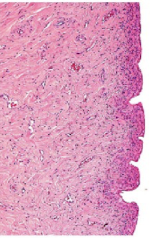

What organ is in the image provided and what phase of the estrous cycle is it in?

vagina in estrus